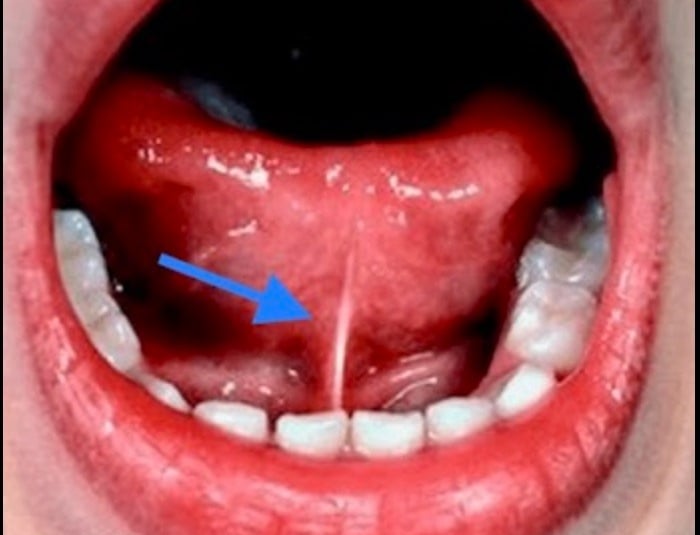

Este pequeño procedimiento, también conocido como frenulectomía lingual, consiste en la eliminación de una banda de tejido que conecta la lengua con la base de la boca.

La cirugía de frenillo lingual en bebés se puede realizar de forma ambulatoria y dura solo unos minutos. Durante la cirugía, el cirujano pediatra corta el frenillo lingual para permitir que la lengua del bebé se mueva libremente.